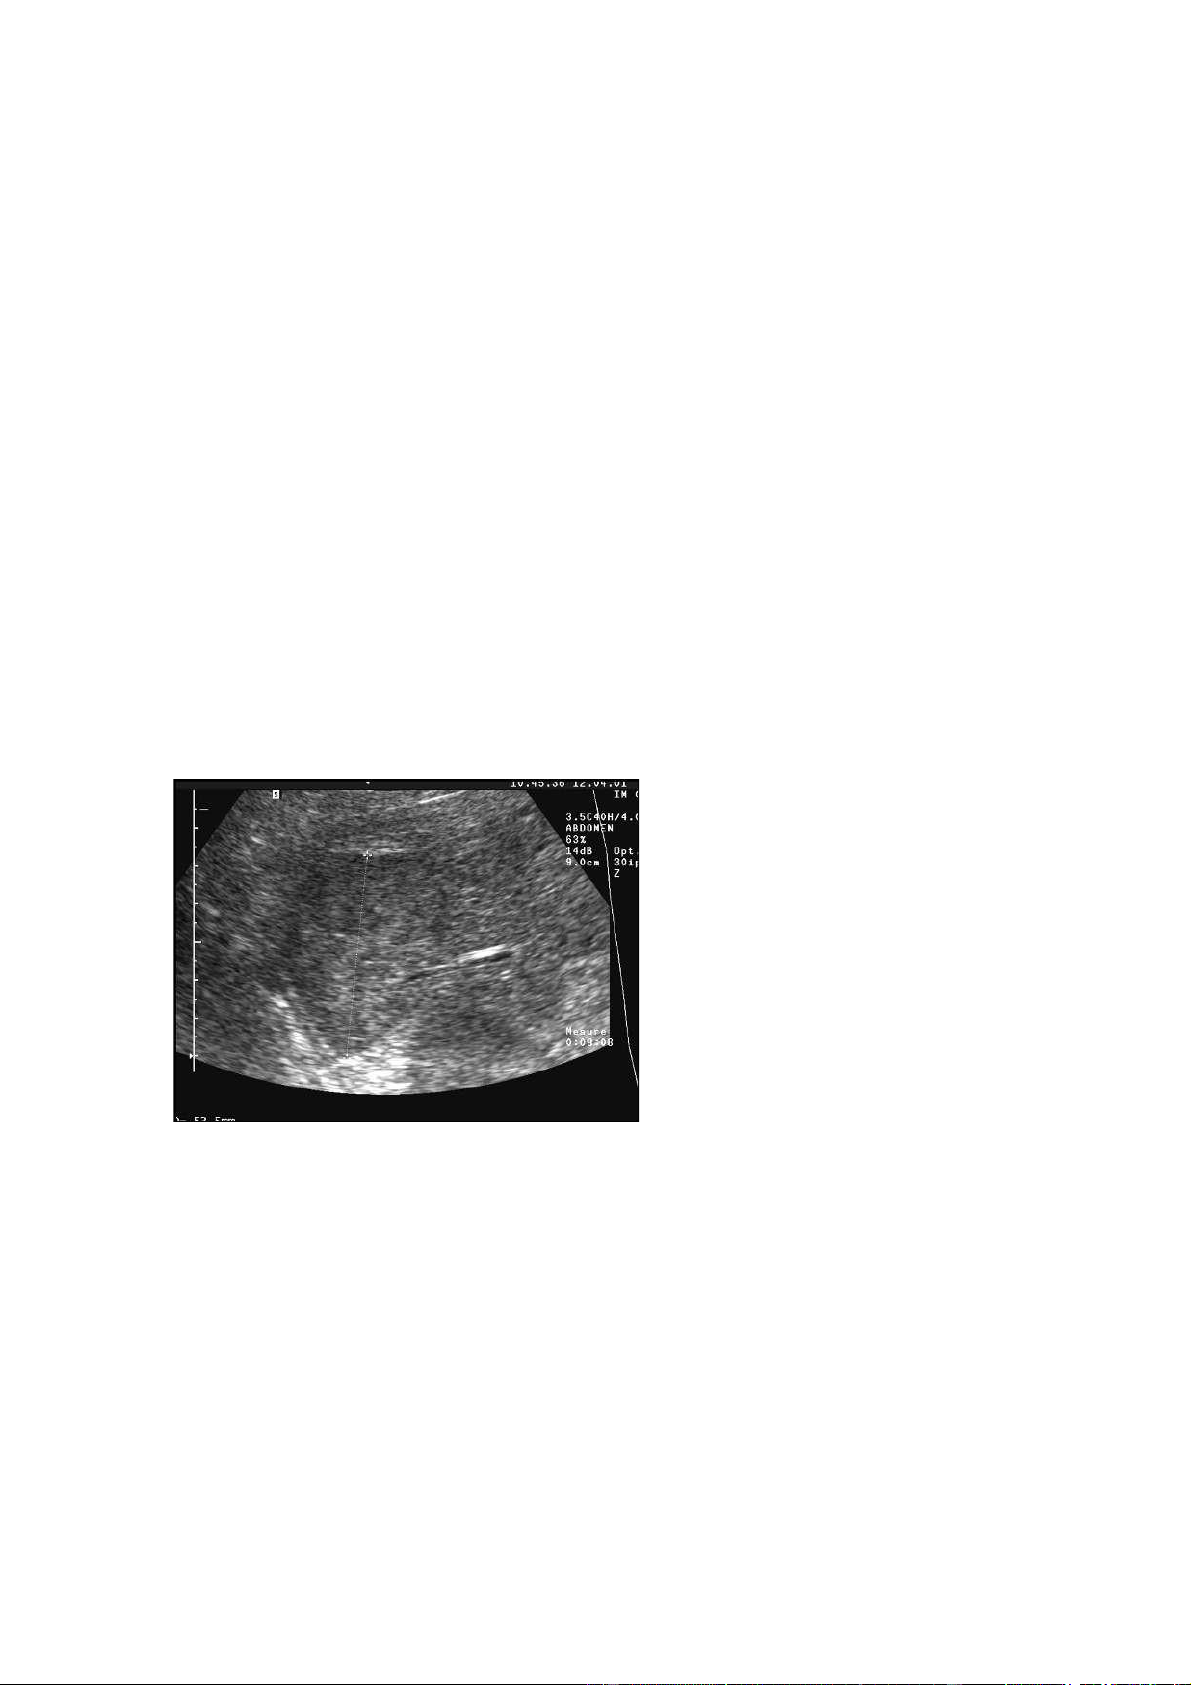

Hình 4.3. a. Siêu âm 2D hình khối đồng

âm với dải tăng âm hình sao trung tâm \